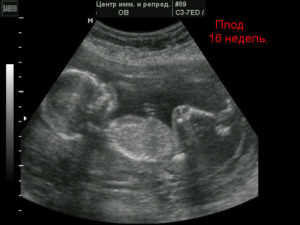

На 16 неделе беременности у женщины проходит токсикоз, интересное положение все больше становится заметно для окружающих.

В это время у будущей мамочки появляется замечательным аппетит, она может ощутить первое шевеление, плод уже имеет достаточный размер для проведения досконального осмотра.

Узи на 16 неделе беременности проводится для того, чтобы обнаружить хромосомные нарушения и врач уже может указать пол ребенка.

16 неделя от момента зачатия относится ко второму триместру беременности и соответствует 18 акушерской неделе. Ультразвуковая диагностика позволяет отследить формирование плода, сопоставляя данные с нормой.

Основная цель процедуры – обнаружение патологий, обусловленных хромосомными отклонениями, тяжелых пороков. На этой стадии основные органы и системы плода достигают достаточных величин для выявления нарушений. Размер малыша позволяет провести доскональный осмотр и оценку развития.